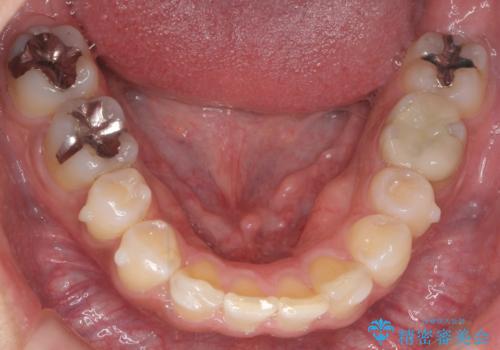

治療終了後、治療前後の写真をお見せすると「全然違いますね!」と喜んで下さいました。

マウスピースを指示された時間通りしっかり装着して下さり、治療中も「もっと長期間つけていても大丈夫なほど違和感ないし、つらくないです」とおっしゃって下さいました。

実際の矯正期間は3ヶ月2週間(マウスピース14枚、1週間交換)と短期間で治療を終えることができました。

装置の種類:インビザライン ライト